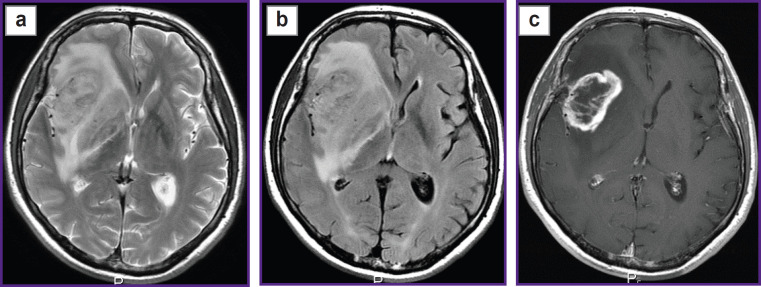

Results: During the investigation, we have developed an algorithm of DKI analysis and plotting the profile of tissue parameters in the direction from the tumor towards the unaffected white matter according to the data of standard MRI. Changes of the DKI indicators along the trajectories built using the proposed algorithm in the perifocal zone of glioblastoma and metastasis have been compared in this work. We obtained not only changes in the parameters (gradients in trajectory plots) but also a visual reflection (on color maps) of a known pathomorphology of the process - no significant gradients of DKI parameters were detected in the perifocal metastasis edema, since there was a pure vasogenic edema and no infiltrative component. In glioblastoma, gradients of DKI parameters were found not only in the zone of perifocal edema but beyond the zone of MR signal as well, which is believed to reflect diffusion disorders along the white matter fibers and different degrees of brain tissue infiltration by glioblastoma cells.

Conclusion: The developed algorithm of DKI analysis in brain tumors makes it possible to determine the degree of changes in the tissue microstructure in the perifocal zone of brain glioblastoma relative to the metastasis. The study aimed at obtaining individual maps of tumor invasion, which will be applied in planning neurosurgical and radiation treatment and for predicting directions of further growth of malignant gliomas.